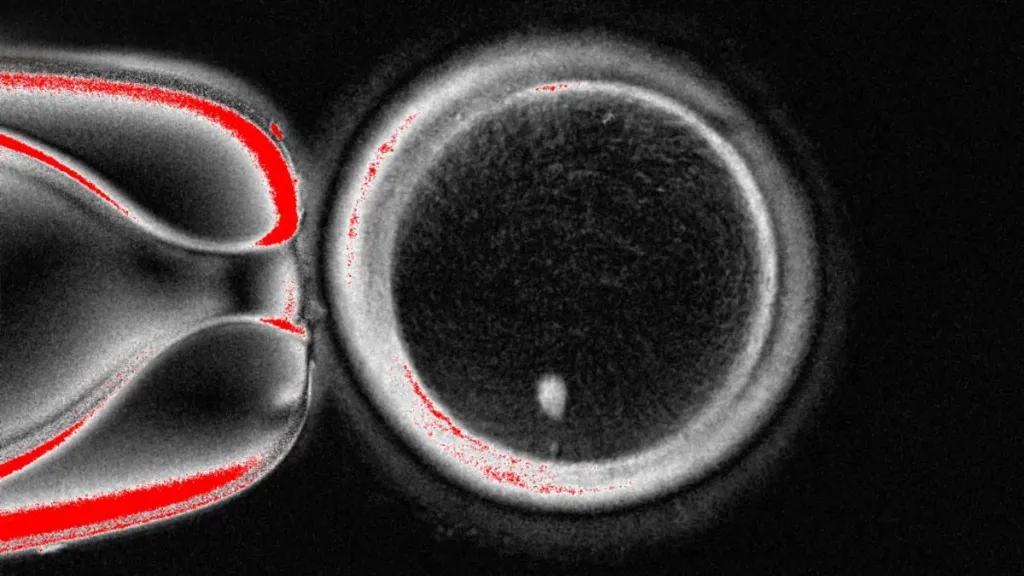

对于单身男性而言,通过辅助生殖技术成为父亲比单身女性面临更多复杂性。莫利纳罗博士解释,单身母亲已拥有子宫和卵子,只需要精子捐赠者即可受孕;而男性则需要同时获得卵子捐赠者和妊娠代孕者。这不仅增加了医疗程序的复杂性,也带来了法律和情感层面的考量。英国的一对富裕夫妇曾展示过极端案例:他们在26岁独子死于摩托车事故两天后,从尸体中提取精子,通过代孕和性别筛查技术创造了一个"孙子"以继承香火。这一案例绕过了英国严格的法律,精子被冷冻后运往美国进行处理。这种死后取精的做法虽然罕见,但凸显了生殖技术的巨大潜力。上海第一妇婴保健院在2023年12月迎来了全球首例成功阻断KIT基因相关疾病的试管婴儿。这名女婴的父亲携带导致异常黑肤色和胃肠道间质瘤的基因突变,而通过第三代试管婴儿技术,成功防止了致病基因的传递。这一突破展示了基因筛查技术与试管婴儿结合的广阔前景。巴斯大学的生物学家们甚至实现了无需卵子受精而繁育健康后代的突破。研究人员将精子注入称为单性繁殖胚胎的无活性胚胎,成功培育出老鼠。这项技术的资深作者托尼·佩里表示,这可能为精子让取自皮肤或其他组织的成年体细胞受精打开大门,甚至可能使两名男性成为婴儿的生物学父母。